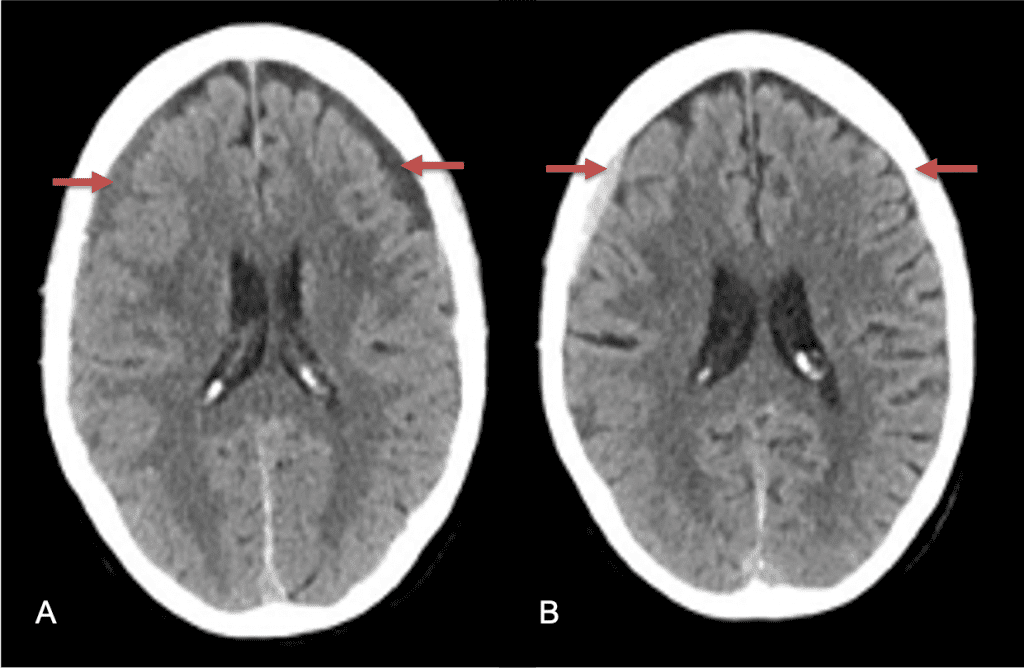

A woman in her 80s developed mild dizziness and headache following incidental trauma working in her garage one day. She presented several weeks later to the ER and was diagnosed with bilateral subdural hematomas, which were initially managed with observation, low dose Decadron, considering the mildness of symptoms, advanced age, and history of CLL with thrombocyptopenia (<100k). Over the next 4 weeks, the collections remained relatively stable with evidence of slight growth (10 to 12 mm thickness, and 2 mm right to left shift) on NCT (Figure 1. A and B).

Figure 1. A) 6 weeks post mild trauma B) 4 weeks post mild trauma demonstrates stable subacute subdural collections with mild growth and sulcal effacement.